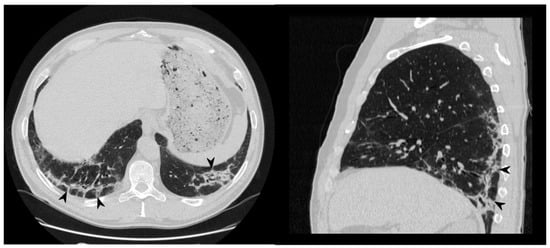

Figure 6. Perilobular pattern: arcade-like bands of parenchymal consolidation (white arrowheads) with blurred borders and thickening of the interlobular septa with a reticular pattern.

1.4. Perilobular Pattern

The perilobular pattern is characterized by curved or arcade-like bands of parenchymal consolidation with blurred borders and thickening of the interlobular septa—resembling a Roman Arch (Figure 6) [22]. It is a perilobular pattern and often associated with other opacities, especially consolidations [17,24]. The presence of air bronchogram sign helps to differentiate this pattern from atelectasis and fibrotic bands; other conditions that must be excluded are post-primary tuberculosis, lymphomatoid granulomatosis, lymphangitic carcinomatosis, fungal infections, sarcoidosis, pulmonary infarction and interstitial edema [33].

Figure 14. On the left: axial view. On the right: sagittal view. Perilobular pattern: the presence of arcade-like bands with blurred borders and thickening of the interlobular septa—resembling a Roman Arch (arrowheads), despite steroid therapy.

One patient—who has shown a perilobular pattern associated with other imaging findings (consolidations and ground-glass opacities)—maintained at follow-up only a residual appearance of this imaging finding. In more detail, a perilobular opacity was still depicted at follow-up CT—with the disappearing of the others (Figure 14). In the other two patients having a perilobular pattern (with a “Roman arch” sign), this imaging appearance was still visible at follow-up HRCT (Table 9), with no modifications.